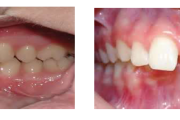

Laste ja noorukite söömishäired. Anorexia nervosa, Bulimia nervosa

Ravijärgne seis. Jäävhammas on täielikult lõikunud.